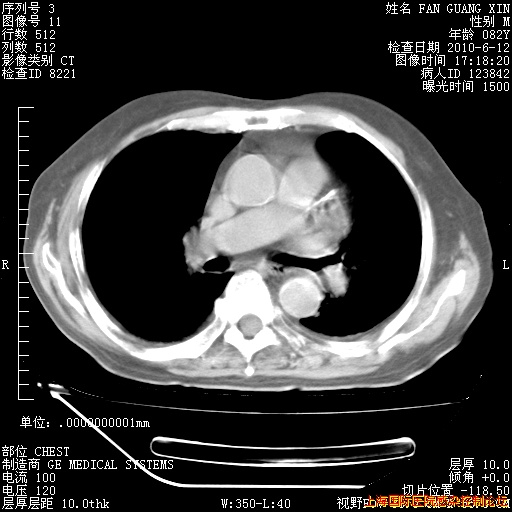

6月12日纵膈窗